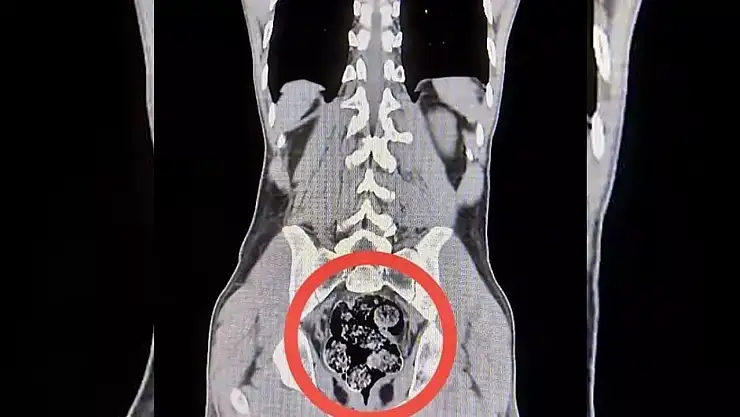

Harakani Devlet Hastanesine götürülen şüphelilerden Amır Rafıeı S'nin mide ve bağırsaklarında 7 parça halinde 203,02 gram sentetik uyuşturucu tespit edildi.